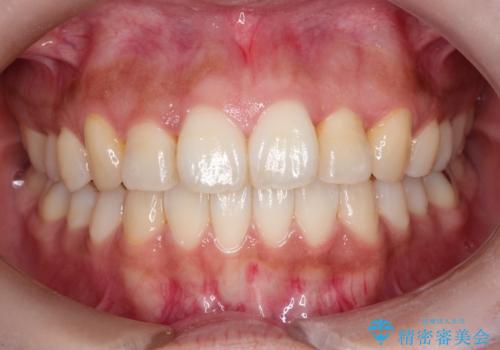

【モニター】八重歯と前歯のクロスバイト ワイヤーを併用しインビザラインで矯正治療